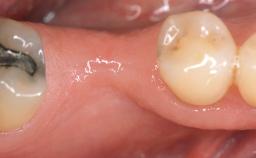

A 30-year-old woman was referred by her general dentist for evaluation of an esthetic complication related to previous implant treatment for congenitally missing maxillary lateral incisors. The patient’s chief complaint was the inadequate esthetic appearance of her smile. The case demonstrates the use of a combined approach to achieve optimal results. Two different flap designs - a tunnel technique and a coronally advanced flap - are employed based on the surgical objectives for the affected site.

Soft Tissue Anatomy Intact Defective

Bone Volume Horizontally and vertically sufficient Horizontally deficient Deficient vertically or deficient vertically AND horizontally